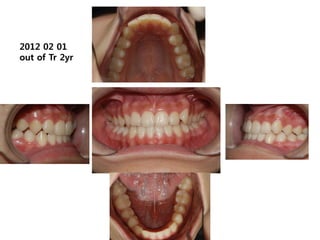

2012 02 01

out of Tr 2yr

1999.11.24 /F

C.C

• Ant. crossbite, crowding

Dx

• Incorrect tongue posture and mentalis action

Goal

• Establish normal tongue posture and swallowing

pattern

2006.09.07

2006.10.27 Start T4K

2007.02.02 4m

2008.01.1

3 1y 3m

2008.10.04 2y

2009.08.04 2y 10m